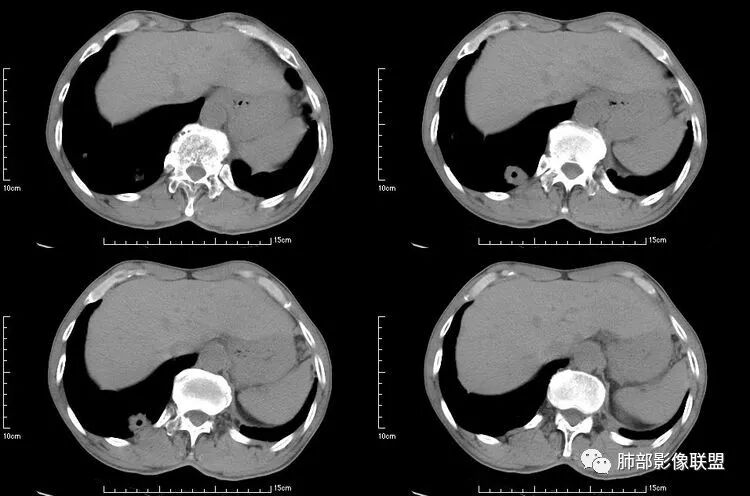

肺是发生转移瘤最多的脏器,几乎所有恶性肿瘤都可转移到肺,血行转移是最重要的转移途径。典型的肺转移瘤表现为多发圆形、大小不一的实性结节,边缘一般光整,多位于肺周边,多能明确诊断。空洞型肺转移瘤相对少见,约占肺转移瘤4%,其中70%为鳞癌转移;常见的空洞型肺转移瘤的原发恶性肿瘤多见于头颈部的鳞状上皮癌、胃肠道的腺癌和女性的生殖系统肿瘤以及其他部位的肉瘤等,组织学以鳞癌和腺癌最多见。

空洞型肺转移瘤成因尚不完全明确, 可能与鳞癌中心角化物排空 、腺癌黏液样退变后黏液排空 、肿瘤血供不足引起坏死 、肿瘤继发脓肿 、化疗等机制有关,其中部分薄壁囊腔样结可能是肿瘤细胞沿着原有的肺大泡或其它囊性结构生长或者肿瘤向小支气管侵犯引起活瓣性阻塞而形成 ,但无一种机制能解释全部现象。空洞或囊腔大小并不反映病情变化, 其临床意义不大, 而瘤灶的数目及大小, 特别是瘤灶实性成分的多少才可能更准确反映病情变化。肺癌形成空洞与其肿瘤本身性质有明显联系,肿瘤分化程度差,倍增时间越短,恶性程度越高,组织液化坏死形成空洞倾向越明显;鳞癌空洞偏大,内缘不规则,常易形成X线平片中癌梁样改变与CT中壁结节样改变;而腺癌空洞大小不定,洞内分隔明显,内缘不规则,且较难于形成壁结节等改变;合伴空洞的肿瘤边缘情况也对判断肿瘤性质有帮助。

本病例左肺下叶肿块,有深分叶、毛刺、胸膜牵拉凹陷、支气管截断及纵隔内淋巴结肿大等征象,都均支持病灶为恶性,如腺癌,而且叶间裂的多发结节也提示是腺癌来源可能大;双肺多发结节、肿块,大部分病灶有分叶、毛刺及胸膜凹陷的恶性征象,与原发肿瘤本身的性质有关,所以应该与左肺下叶肿块同源,而且双肺多发病灶内空洞也具有多样性;